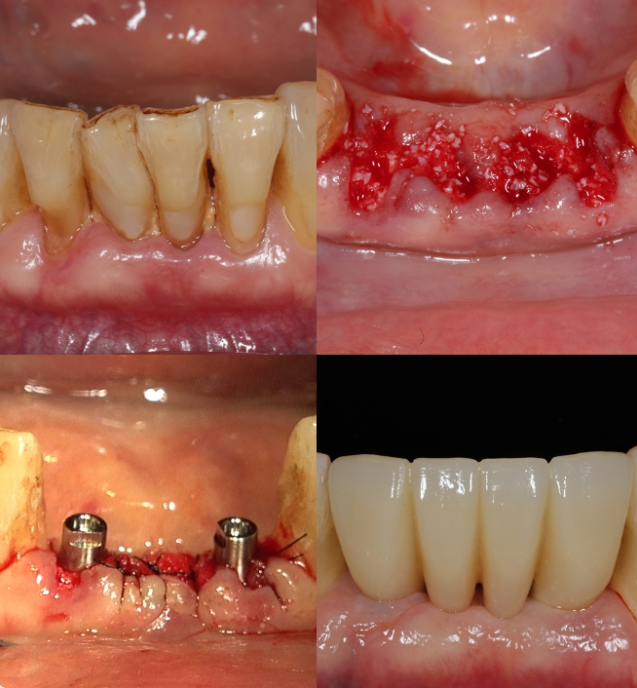

Concept 3SurgeryEasy Bone Graft

Use Only What’s Needed, Create more than expected

Simple and Easy Bone Grafting, Predictable Results- Streamlined, efficient

Skip unnecessary steps - Just a straightforward process that makes it easy for both the clinician and the patient

- Less Material, More Impact

Biocompatible regenerative materials used precisely as needed – for stable, predictable outcomes.

- Optimized for Recovery

Shorter and simple procedures with less post operative pain and faster healing